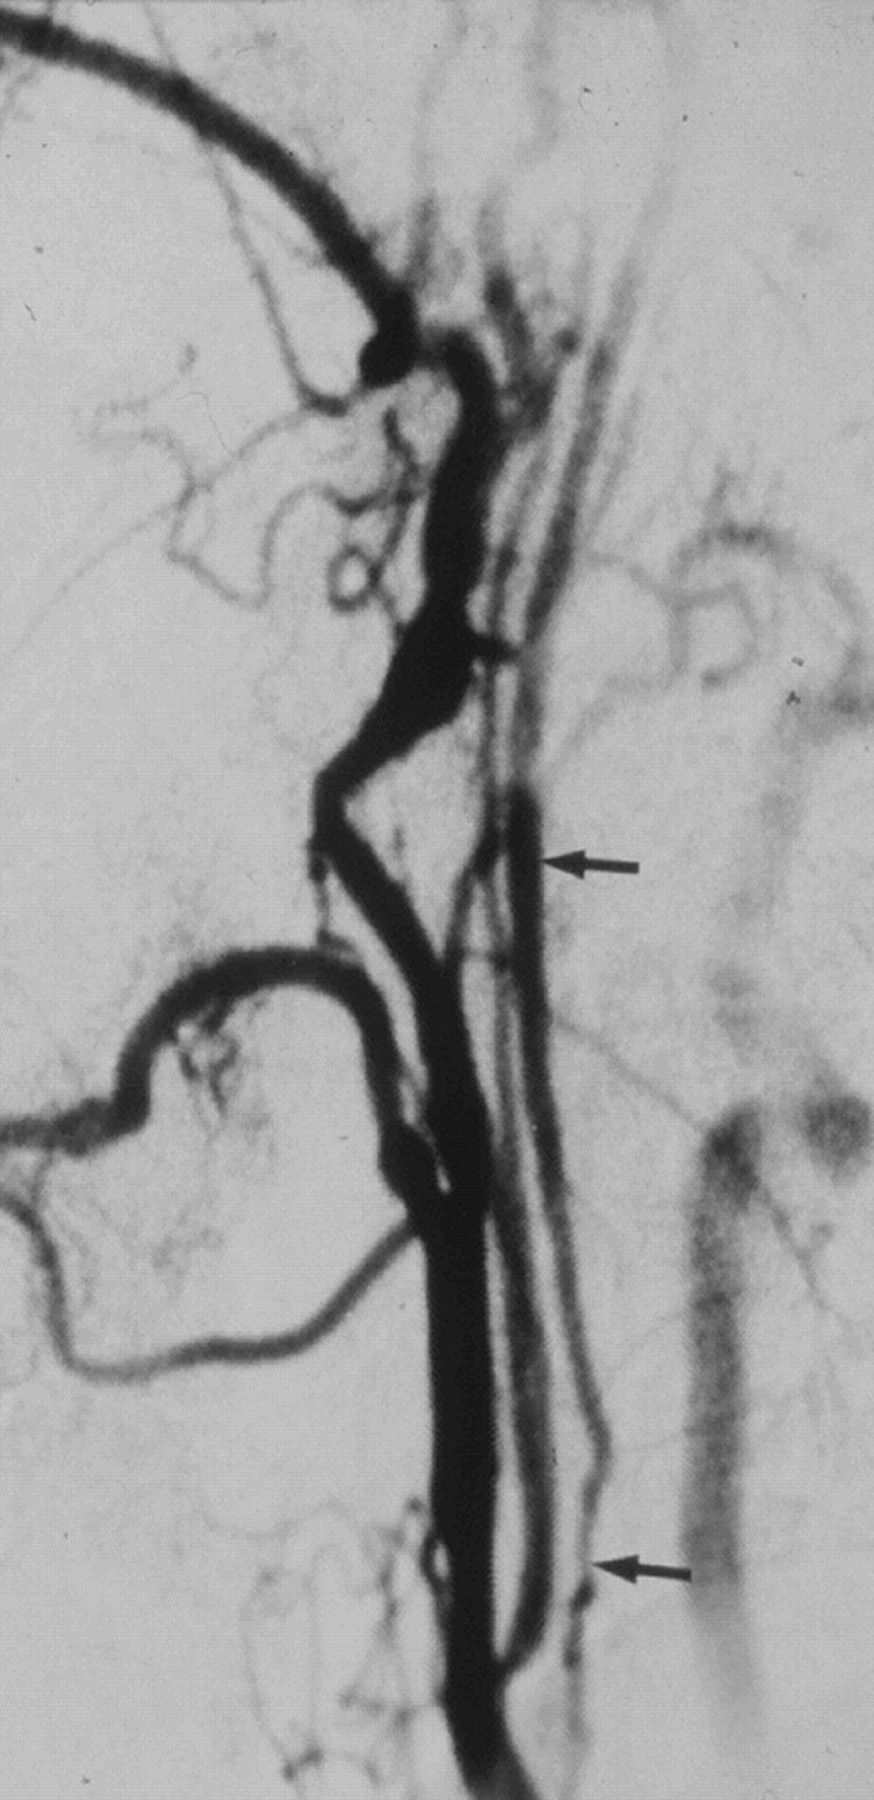

A case with near-occlusion without full collapse, reprinted with permission from Fox et al.1 Lateral carotid angiogram shows a reduced ICA lumen distal to the stenosis (larger arrow); the diameter is slightly less than the ECA diameter (smaller arrow). The distal ICA lumen is normal-appearing (not threadlike).